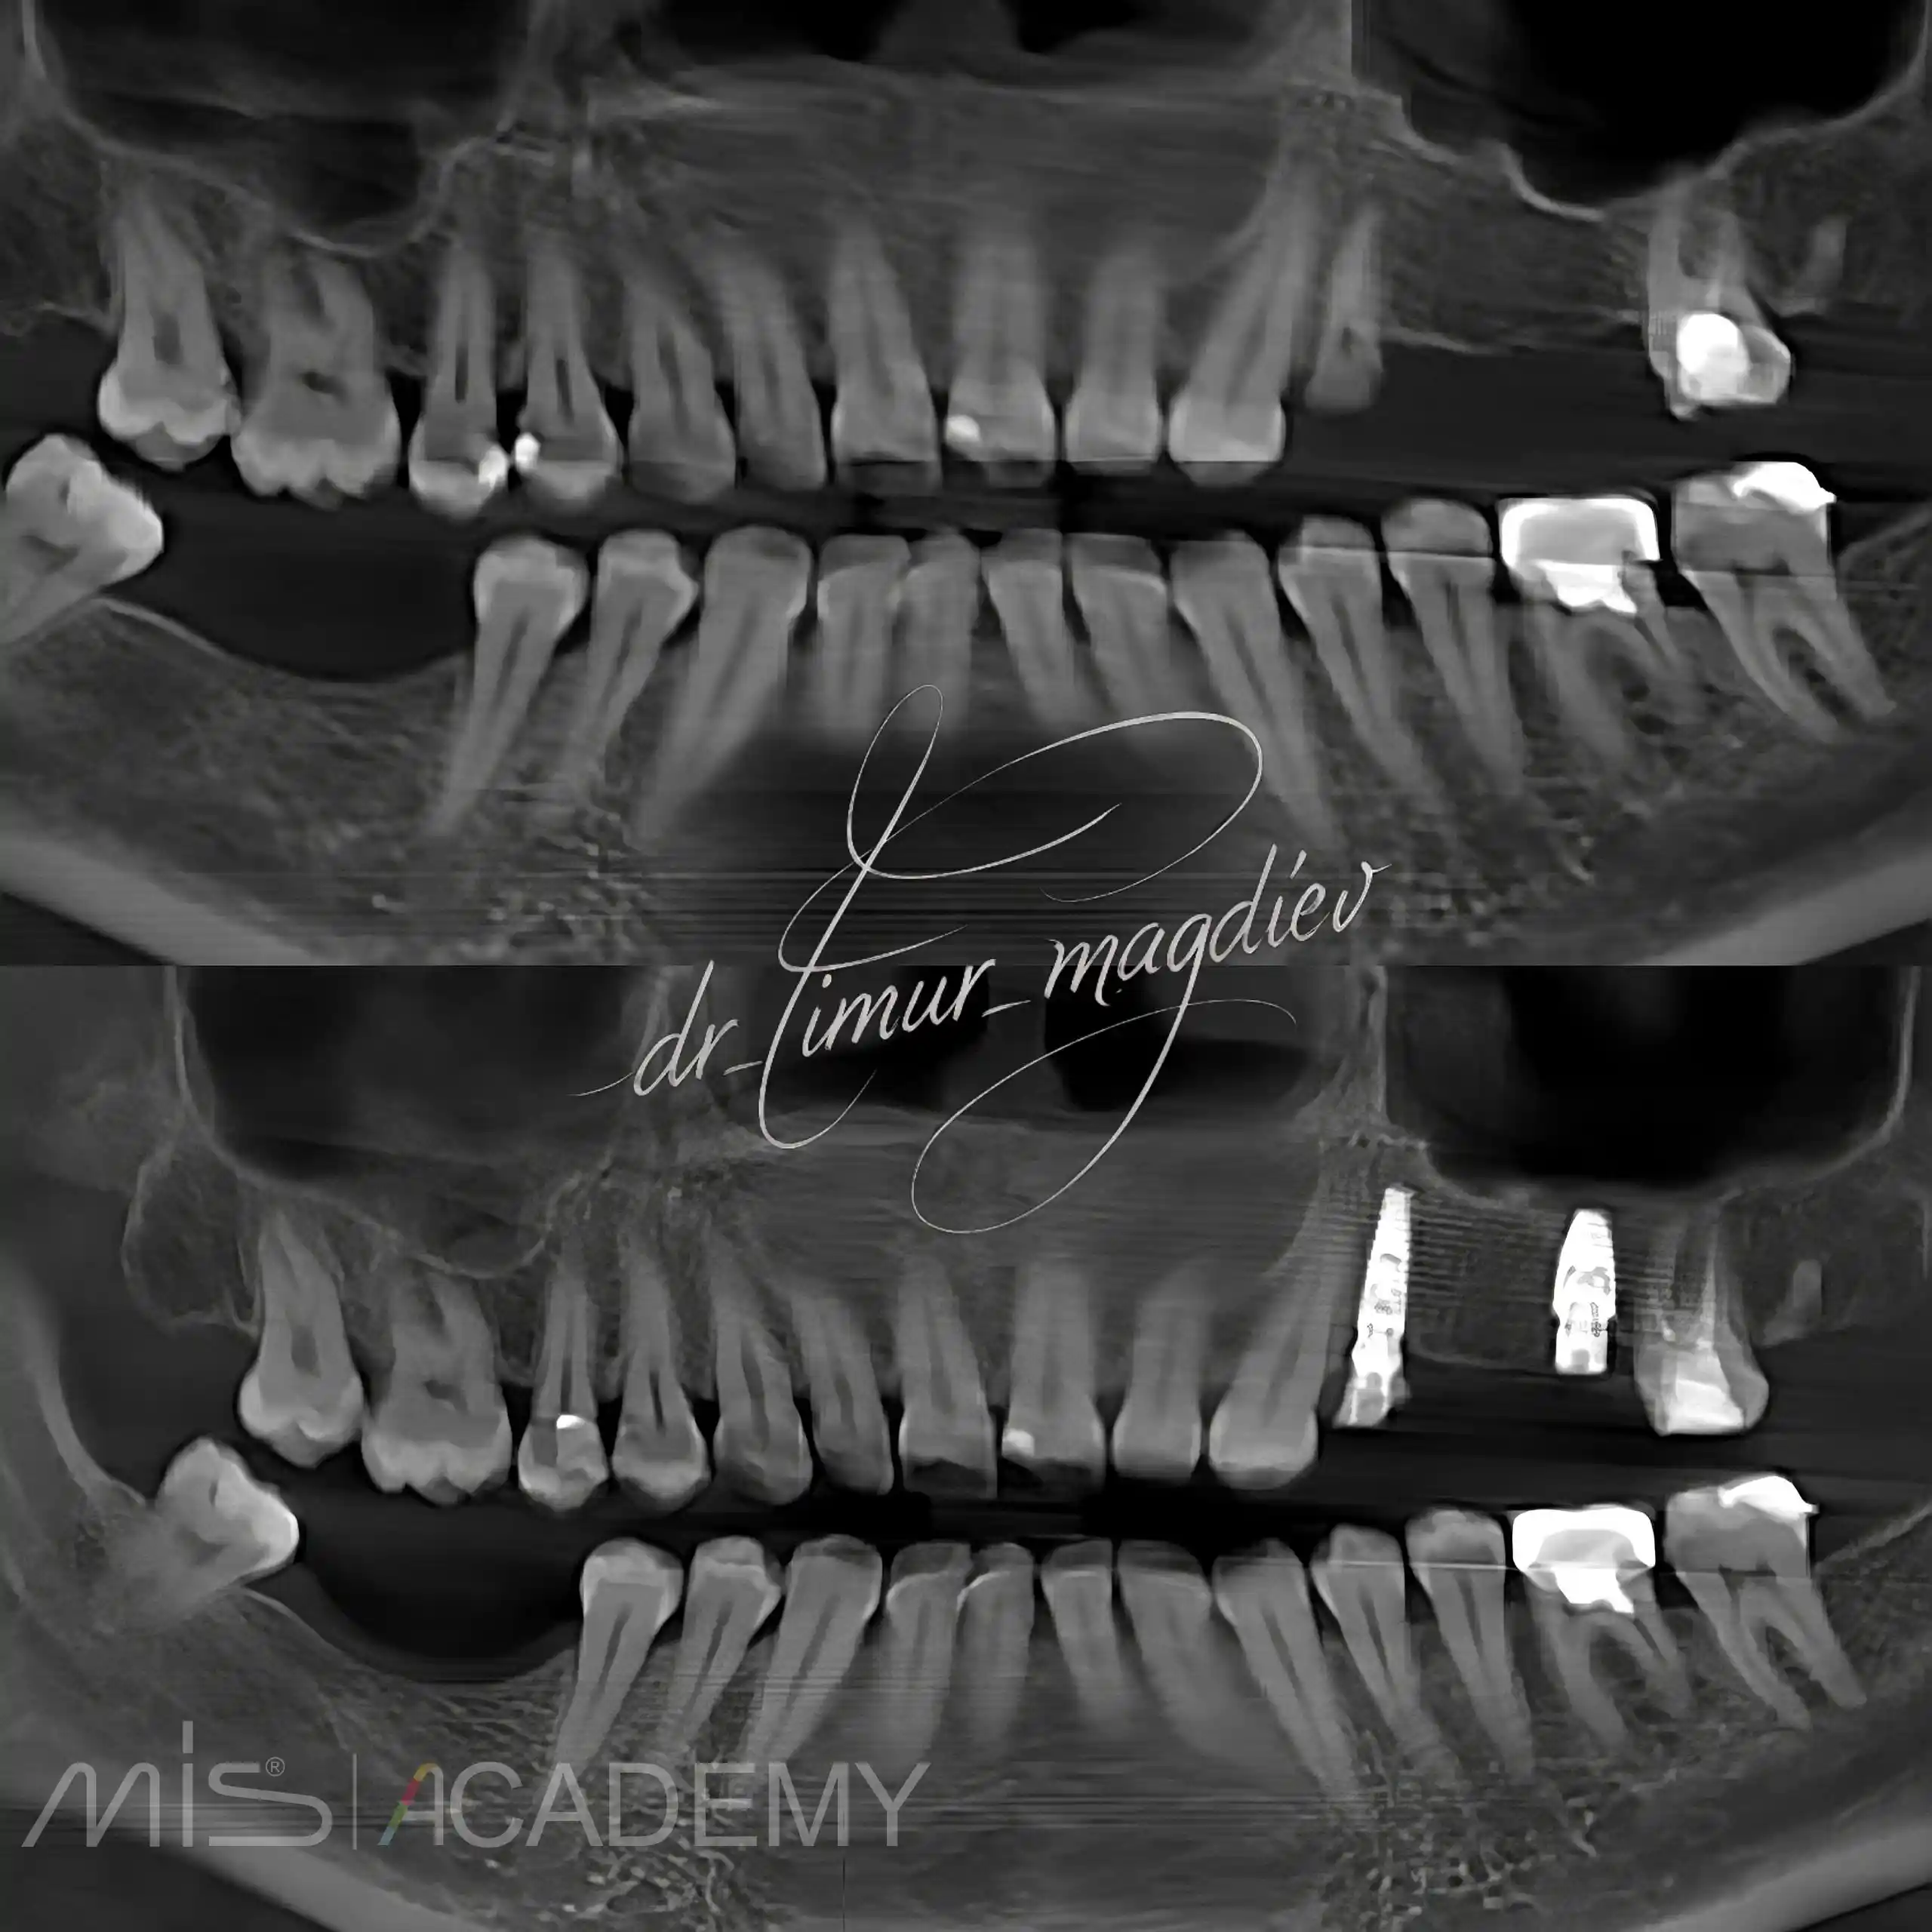

— Установка имплантатов MIS C1 + Connect в полном навигационном протоколе.

— 24 одномоментно IDR.

— 26 отсрочено.

Протезирование: Сергей Александрович Белоборотцев.